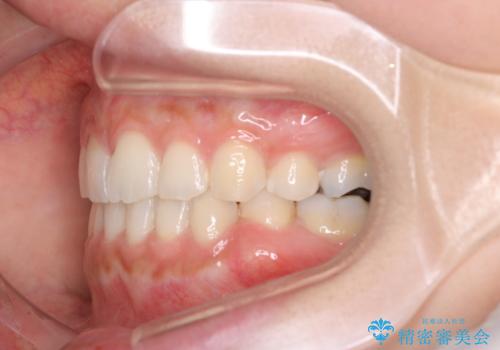

- 口元が出てるのが気になるとのことで来院されました。

上下左右前から4番目の歯を抜歯して前歯を後方に下げて、口元を下げる計画としました。

口元を大きく改善したい場合は抜歯が必要となることが多いです。